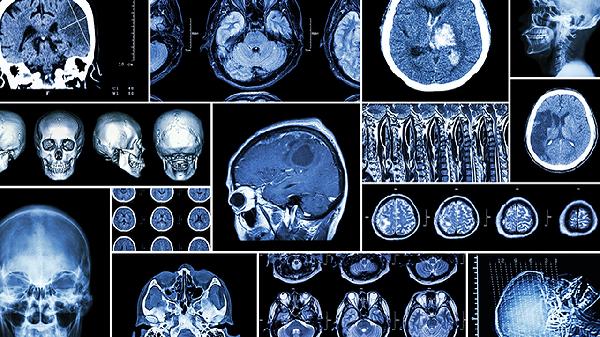

脑血栓可通过生活干预、药物治疗、手术治疗等方式治疗。脑血栓通常由动脉粥样硬化、高血压、糖尿病、心房颤动、高脂血症等原因引起。

注射用阿替普酶适用于发病4.5小时内的急性期患者,需排除出血风险后使用。尿激酶注射液可通过激活纤溶酶原溶解血栓,治疗时间窗可延长至6小时。使用期间需密切监测神经系统症状变化。

颈动脉内膜切除术适用于颈动脉狭窄超过70%的无症状患者。机械取栓术通过导管介入清除大血管血栓,最佳实施时间为发病6小时内。部分大面积脑梗死患者可能需去骨瓣减压术降低颅内压。